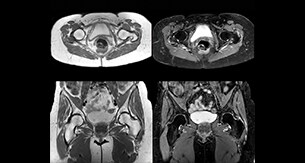

1. Diagnostic imaging

2. Magnetic resonance imaging

Magnetic resonance imaging

Patient-centric MRI equipment and solutions

At Philips, our mission is to enable fast, fully automated, and personalized MR exams for every patient while acting responsibly toward our planet and society. Through AI-driven smart connected imaging, optimized workflows, and integrated clinical solutions, we improve your MR department’s productivity, enhance the experience for both patients and staff, and deliver high-quality diagnostic outcomes.